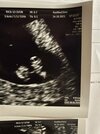

Gratulacje dziewczyny, pochwalcie się jaki miałyście crlJa jestem właśnie po wizycie u lekarza. Według usg 6+1 według aplikacji 6+4. Najważniejsze, ze serduszko bije i wszystko jest okej. Teraz tylko badania i wizyta kolejna na 28.10![]()